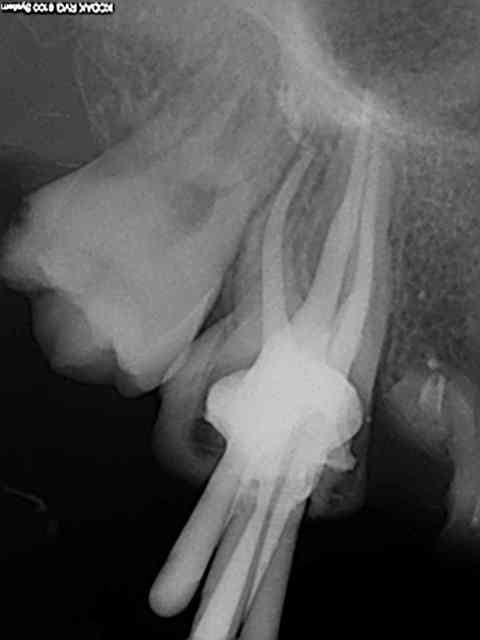

Ca n'arrive pas à chaque fois. Comme ca c'est mieux ?

Un peu. Tu as tendance à ne pas savoir te retenir. Un obturateur précoce, en quelque sorte.